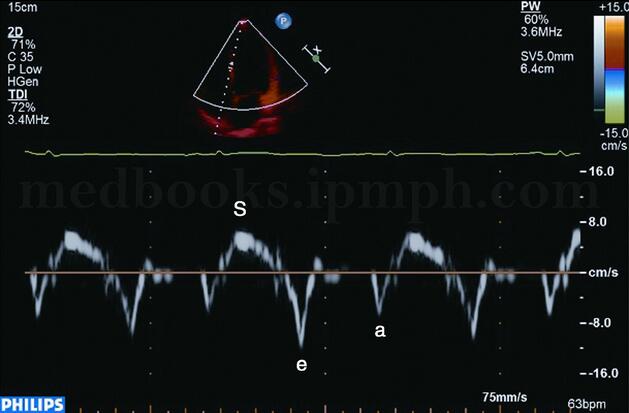

多普勒心肌组织成像直接提取的是低速、高振幅的室壁运动信息,包括组织速度显像、组织追踪显像、能量图和应变及应变率成像等。组织速度显像包括彩色二维或多普勒频谱速度图显示,前者用不同的色彩覆盖相应速度的心肌,可以较快速地识别室壁运动的方向和速度,提高目测判断的准确性;后者设置取样容积于某一节段,将该节段的心肌运动速度直接显示在频谱图像上,定量显示心肌的收缩和舒张速度(图2‐1‐154,图2‐1‐155)。

图2‐1‐154 正常人心肌组织速度图,心尖四腔心切面彩色二维显像

图2‐1‐155 正常人心肌组织速度图,间壁中间段纵向频谱速度显像